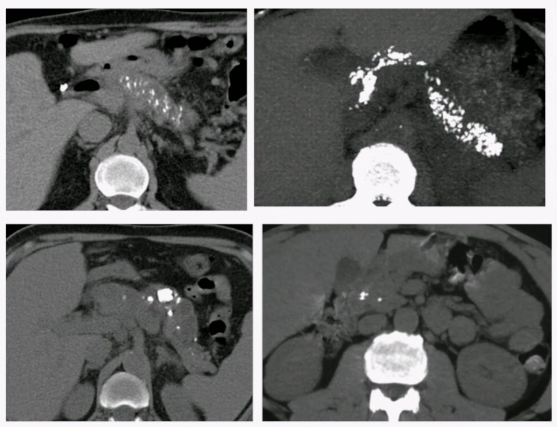

CT

- Atrophie pancréatique

- Calcifications

- Irrégularités du Wirsung, Dilatations - Sténoses

- Cancer (hypodensité focale, dur a différencier de la pseudomasse inflammatoire, chercher les signes indirects type dilatation canalaire majorée, ecartement des calcifications)

- Complications chroniques d’épisodes de pancréatites aigues